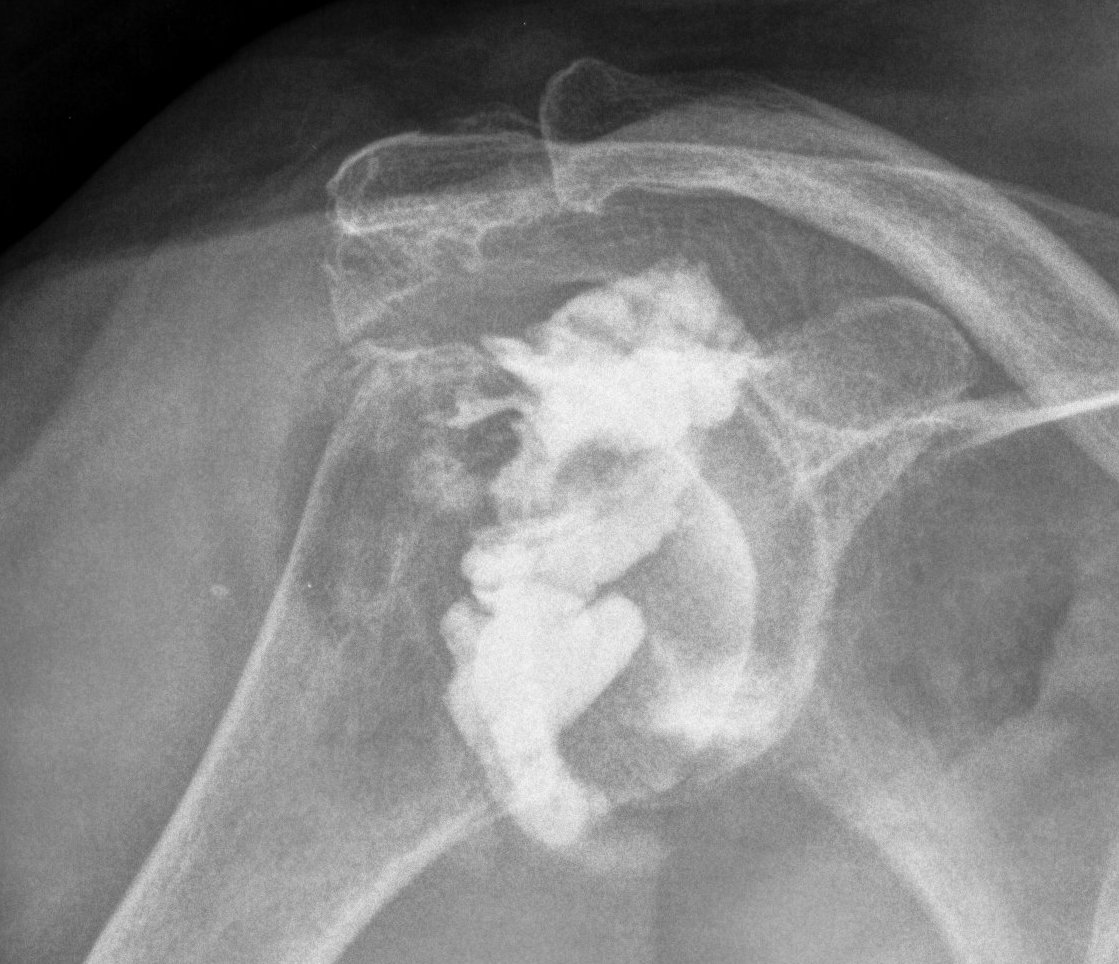

From www.ctisus.com

Rotator Cuff Tear on Shoulder Arthrogram X Rays Case Studies CTisus Shoulder Arthrogram Images Glenohumeral arthrography, shoulder arthrography, is an imaging technique used in evaluating the glenohumeral joint. The contrast that is injected into your. On the internal rotation view (figure 3.6) the superior surface of the cuff is demonstrated but is. This page details a normal anatomy of the glenohumeral joint and of the rotator cuff on a mr arthrography of the shoulder:. Shoulder Arthrogram Images.